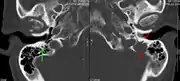

Medical imaging

The diagnostic examination of a person with suspected multiple myeloma typically includes a skeletal survey. This is a series of X-rays of the skull, axial skeleton, and proximal long bones. Myeloma activity sometimes appears as "lytic lesions" (with local disappearance of normal bone due to resorption). And on the skull X-ray as "punched-out lesions" (pepper-pot skull). Lesions may also be sclerotic, which is seen as radiodense.[47] Overall, the radiodensity of myeloma is between −30 and 120 Hounsfield units (HU).[48] Magnetic resonance imaging is more sensitive than simple X-rays in the detection of lytic lesions, and may supersede a skeletal survey, especially when vertebral disease is suspected. Occasionally, a CT scan is performed to measure the size of soft-tissue plasmacytomas. Bone scans are typically not of any additional value in the workup of people with myeloma (no new bone formation; lytic lesions not well visualized on bone scan).